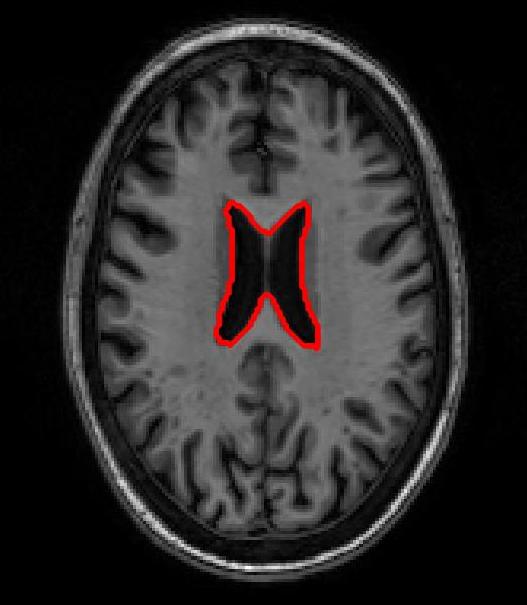

FigureΒ 3 shows results for brain image registration. We show the reference image in FigureΒ 3 (a) followed by an example floating image in FigureΒ 3 (b). The ventricle structure to be aligned is shown in red in both images. FigureΒ 3 (c)-(e) shows the deformed structures obtained by applying the registration field obtained from different methods to the floating image and superimposing these structures on the atlas image. The deformed structures from the floating image are shown in blue. In case of perfect registration the blue and red contours should coincide. In this case SR-Net actually does better than VoxelMorph, while SR-Net does significantly worse due to absence of segmentation information.

![]() |

| (a) | (b) | (c) | (d) | (e) |